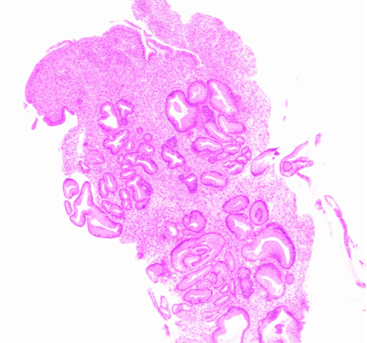

胃镜检查:胃体下部-胃角-部分胃窦可见低回声团块,腹腔存在多发肿大淋巴结。(胃窦咬检)病理:低分化腺癌;免疫组化:HER2(2+),MLH1(+),PMS2(+),MSH2(+),MSH6(+),PD-L1 CPS=1(图1)。

20.1.png图1. 胃窦病理检查